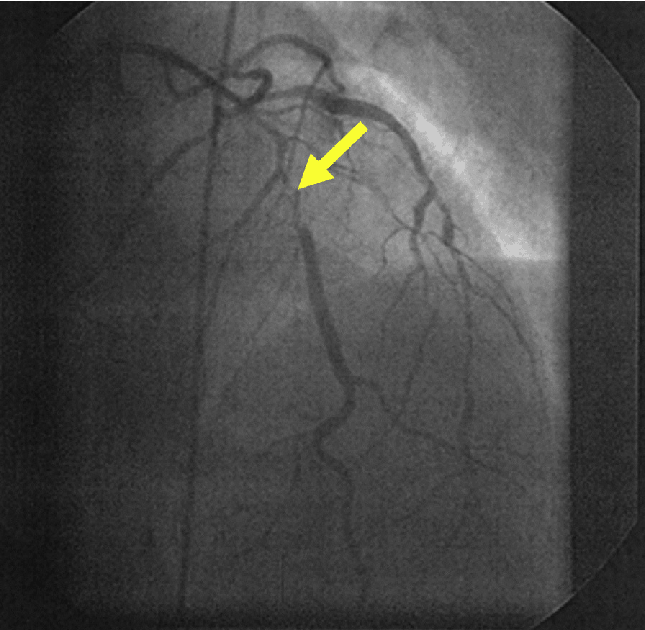

Анатомия коронарных артерий: КТ-изображения